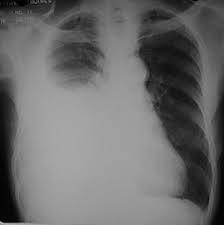

Question

La patología que se visualiza en la imagen se le denomina

Answer

• Edema

• Ascitis

• Derrame abdominal

• hiperemia